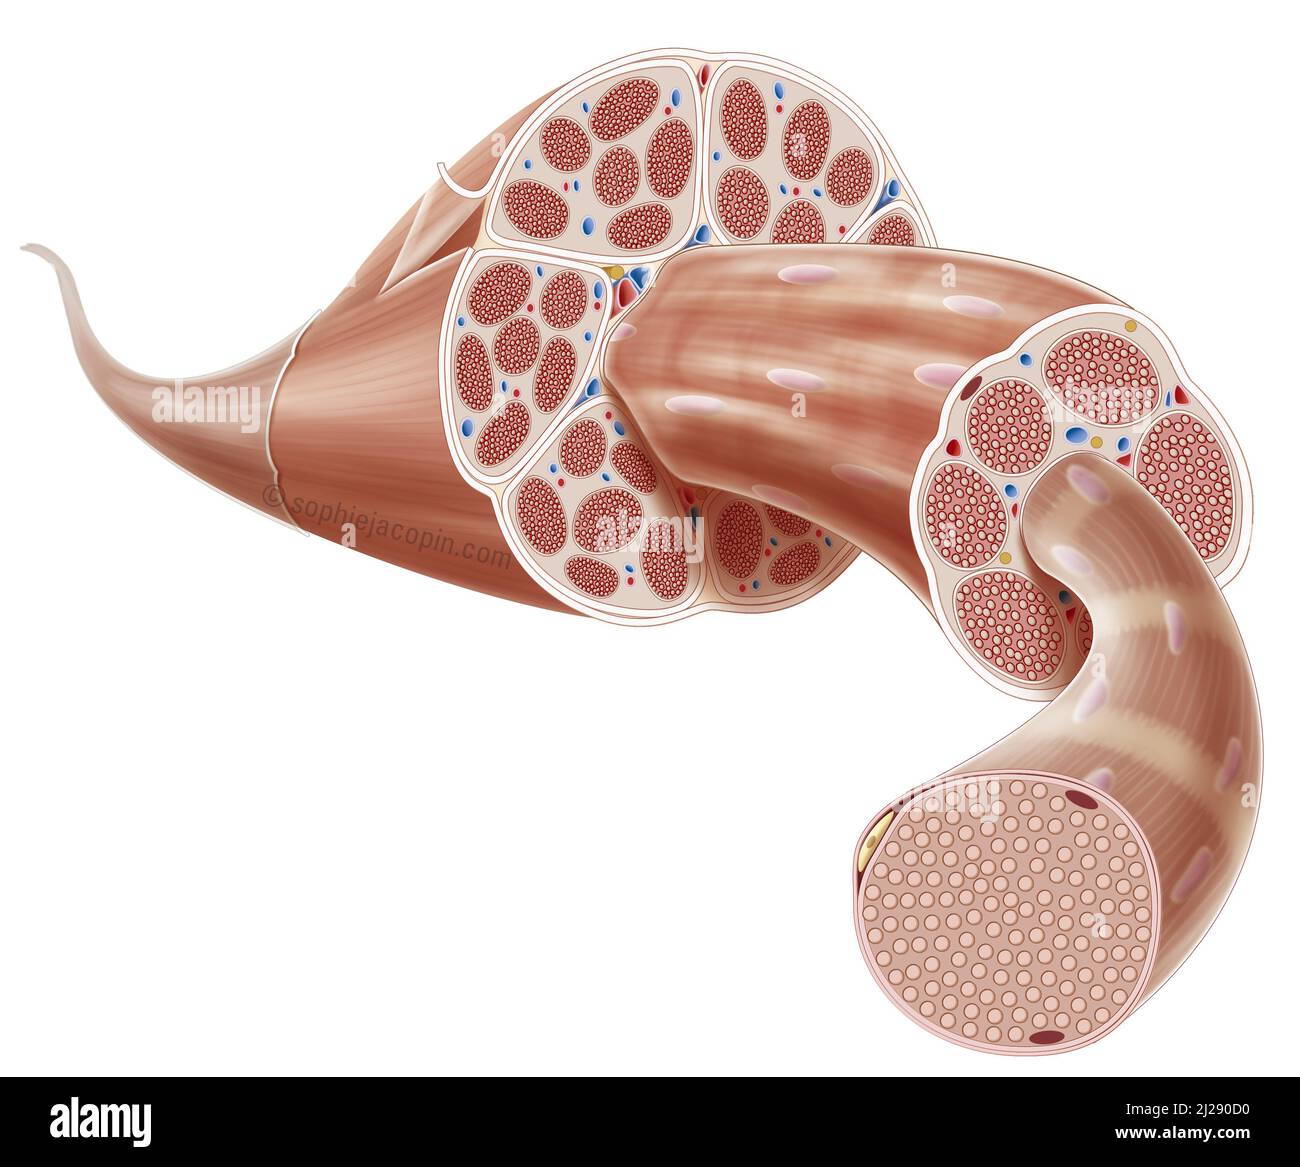

Muscle structure Stock Photohttps://www.alamy.com/image-license-details/?v=1https://www.alamy.com/muscle-structure-image466107180.html

Muscle structure Stock Photohttps://www.alamy.com/image-license-details/?v=1https://www.alamy.com/muscle-structure-image466107180.htmlRM2J290D0–Muscle structure